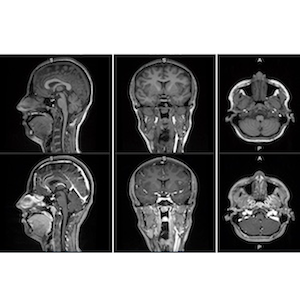

Photo: GE HealthCare

Mangaciclanol is intended for general-purpose MR imaging and demonstrates comparable relaxivity (the ability to enhance signal intensity) to gadolinium-based agent, gadobutrol, with early clinical images suggesting similar diagnostic capability. Unlike gadolinium, which is a rare-earth metal, manganese is present in our food, and is an endogenous element, naturally occurring and autoregulated in the body. The macrocyclic "cage-like" structure of mangaciclanol lessens the possibility of retention.